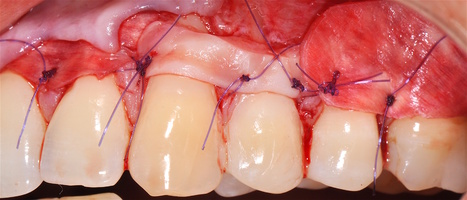

1. Генерализованные рецессии в области нижней челюсти оперировались в один этап все 12 зубов, фронтальный участок с аутотрансплантатом от 3.2 до 4.2 зубов. А дистальные участки от 3.6 до 3.3 и от 4.6 до 4.3 зубов с использованием пластического материала ТМО (dura mater) (рис. 4а-з).

Участки 3.3-3.6 зубов и 4.3-4.6 зубов были проопери- рованы зеркально по методу коронально-ротированно- го лоскута по M. De Sanctis и G. Zucchelli (2000) с одним послабляющим вертикальным разрезом в области 3.3 зуба или 4.3 зуба.

4. Фиксация пластического материала ТМО (dura mater) к поверхности корней зубов в области зоны создания необходимого объема прикрепленной десны.

5. Закрытие пластического материала слизисто-надкостничным лоскутом со смещением в корональном направлении, и фиксация слизисто-надкостничного лоскута швами; дополнительная фиксация зоны перемещенных и в будущем созданных мягких тканей десны в зоне рецессии десны для стабилизации результата операции.

Деэпителизация анатомических сосочков, обработка поверхностей корней зубов, фиксация свободного десневого аутотрансплантата и пластического материала ТМО (dura mater) швами, с полным перекрытием слизисто-надкостничным лоскутом, фиксация швами слизисто-надкостничного лоскута узловыми одиночными швами в области установки аутотрансплантата и ТМО (dura mater), двойными обвивными для слизисто-надкостничного лоскута, и крестообразными прижимающими горизонтальными швами для фиксации слизисто-надкостничного лоскута в новом положении. Обработка поверхностей корней зубов проводилась аналогично.